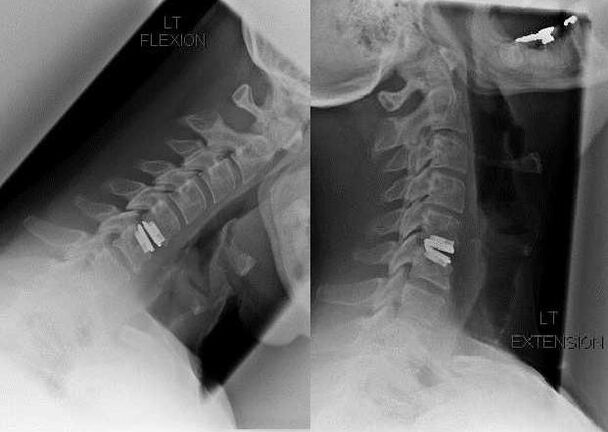

Intervención quirúrgica

Las indicaciones para la intervención quirúrgica incluyen la ineficacia del tratamiento conservador, así como las complicaciones de la osteocondrosis cervical, por ejemplo, mielopatía discogénica, síndrome de la arteria vertebral y síndrome radicular. Para reducir la médula espinal, los vasos sanguíneos y las raíces espinales, se realizan las siguientes operaciones:

Durante la cirugía, se pueden extirpar fragmentos óseos y ligamentos, y se puede extirpar total o parcialmente el disco intervertebral. Para pequeñas protuberancias herniarias, a menudo se realiza la vaporización con láser del núcleo del disco.

Después del aislamiento de las estructuras vertebrales, a menudo se requiere la estabilización de los segmentos de movimiento de la columna mediante fusión espinal o instalación de autoinjertos óseos y dérmicos.